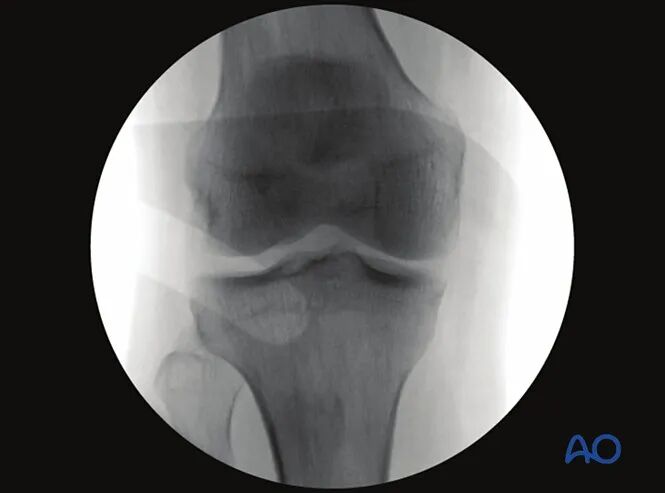

2. 胫骨近端前后位

最佳影像的验证标准

满足以下条件即为胫骨近端最佳前后位影像:

●髌骨尖正对股骨髁间窝中心;

●腓骨头与胫骨近端外侧缘的重叠范围占腓骨头的1/4至1/3;

●射线束中心点对准胫骨平台。

可识别的解剖标志与线条

胫骨近端前后位影像中可清晰识别的解剖标志与线条包括:

1.外侧胫骨平台、

2.髌骨、

3.腓骨头、

4.内侧胫骨平台、

5.外侧胫骨棘、

6.内侧胫骨棘。

临床观察要点

该体位尤其适用于判断以下情况:

●关节内骨折复位不良(关节面台阶征);

●关节内植入物位置;

●内翻或外翻应力下关节间隙增宽(提示侧副韧带损伤);

●胫骨棘撕脱骨折(提示交叉韧带损伤);

●关节面与胫骨长轴的夹角是否正常(正常范围85°-90°)。

可拍摄健侧肢体影像作为对照参考。